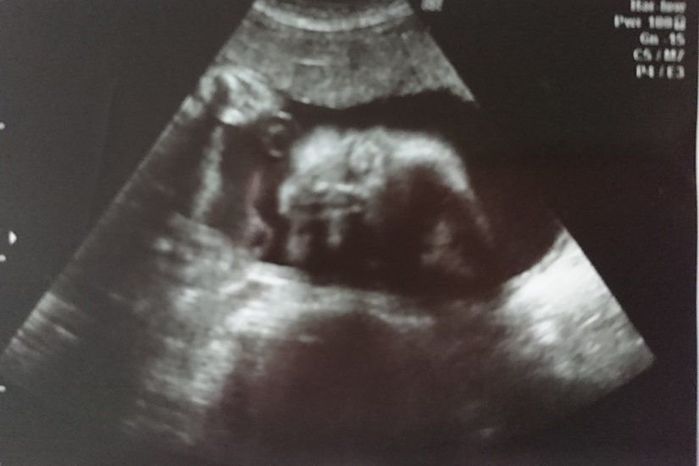

妊娠31週目のエコー写真

ふっくらと顔も体も丸みをおびてきました。3D画像は、横顔がはっきりと写っていて、手をギュっと握っているのが分かります。今の息子の寝顔にそっくりだと、改めて思いました。この頃の体の悩みは、腰痛と脚のむくみでした。家に帰り着圧ソックスを履くとかなり楽になりました。赤ちゃんの推定体重は1648gでした。